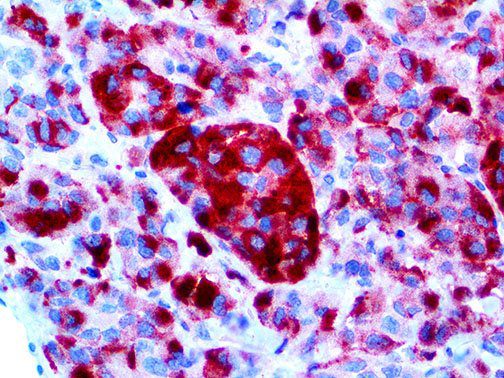

It is the ICU physician who is most likely to witness one of the deadliest manifestations of the abnormal immunological response, the cytokine storm syndrome (CSS). This response is also referred to by some as the cytokine release syndrome (CRS). CSS is characterized by continuous activation and expansion of macrophage and lymphocyte populations, which secrete large amounts of cytokines, causing the cytokine storm. This massive cytokine release is akin to hemophagocytic lymphohistiocytosis (HLH) disease, a syndrome characterized by initial unchecked and persistent activation of cytotoxic T lymphocytes and NK cells.

Clinical and laboratory manifestations of HLH include fever, enlarged liver and/or spleen, neurologic dysfunction, coagulopathy, liver dysfunction, cytopenias (i.e., low levels of erythrocytes, leukocytes, and/or platelets), hypertriglyceridemia, hyperferritinemia, hemophagocytosis, and eventually diminished NK cell activity as the immune system becomes progressively paralyzed. HLH can be familial (primary HLH) or secondary to another disease process (sHLH), such as rheumatic disease, in which it is referred to as macrophage activation syndrome (MAS, characterized by elevated ferritin).